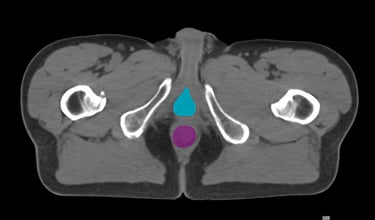

The DAM Contour features a comprehensive collection of OARs and CTVs that are ready for immediate use, without the need for manual creation of atlases or manual adjustment of data. This product includes all standard OAR and CTV structures (over 117 in total).

The Pelvis lymph node region encompasses lymph nodes that include the obturator lymph nodes, internal and external iliac lymph nodes (limited anteriorly at the level of the femoral heads), and extends up to the common iliac lymph nodes, covering the L5/S1 region.

Pelvis